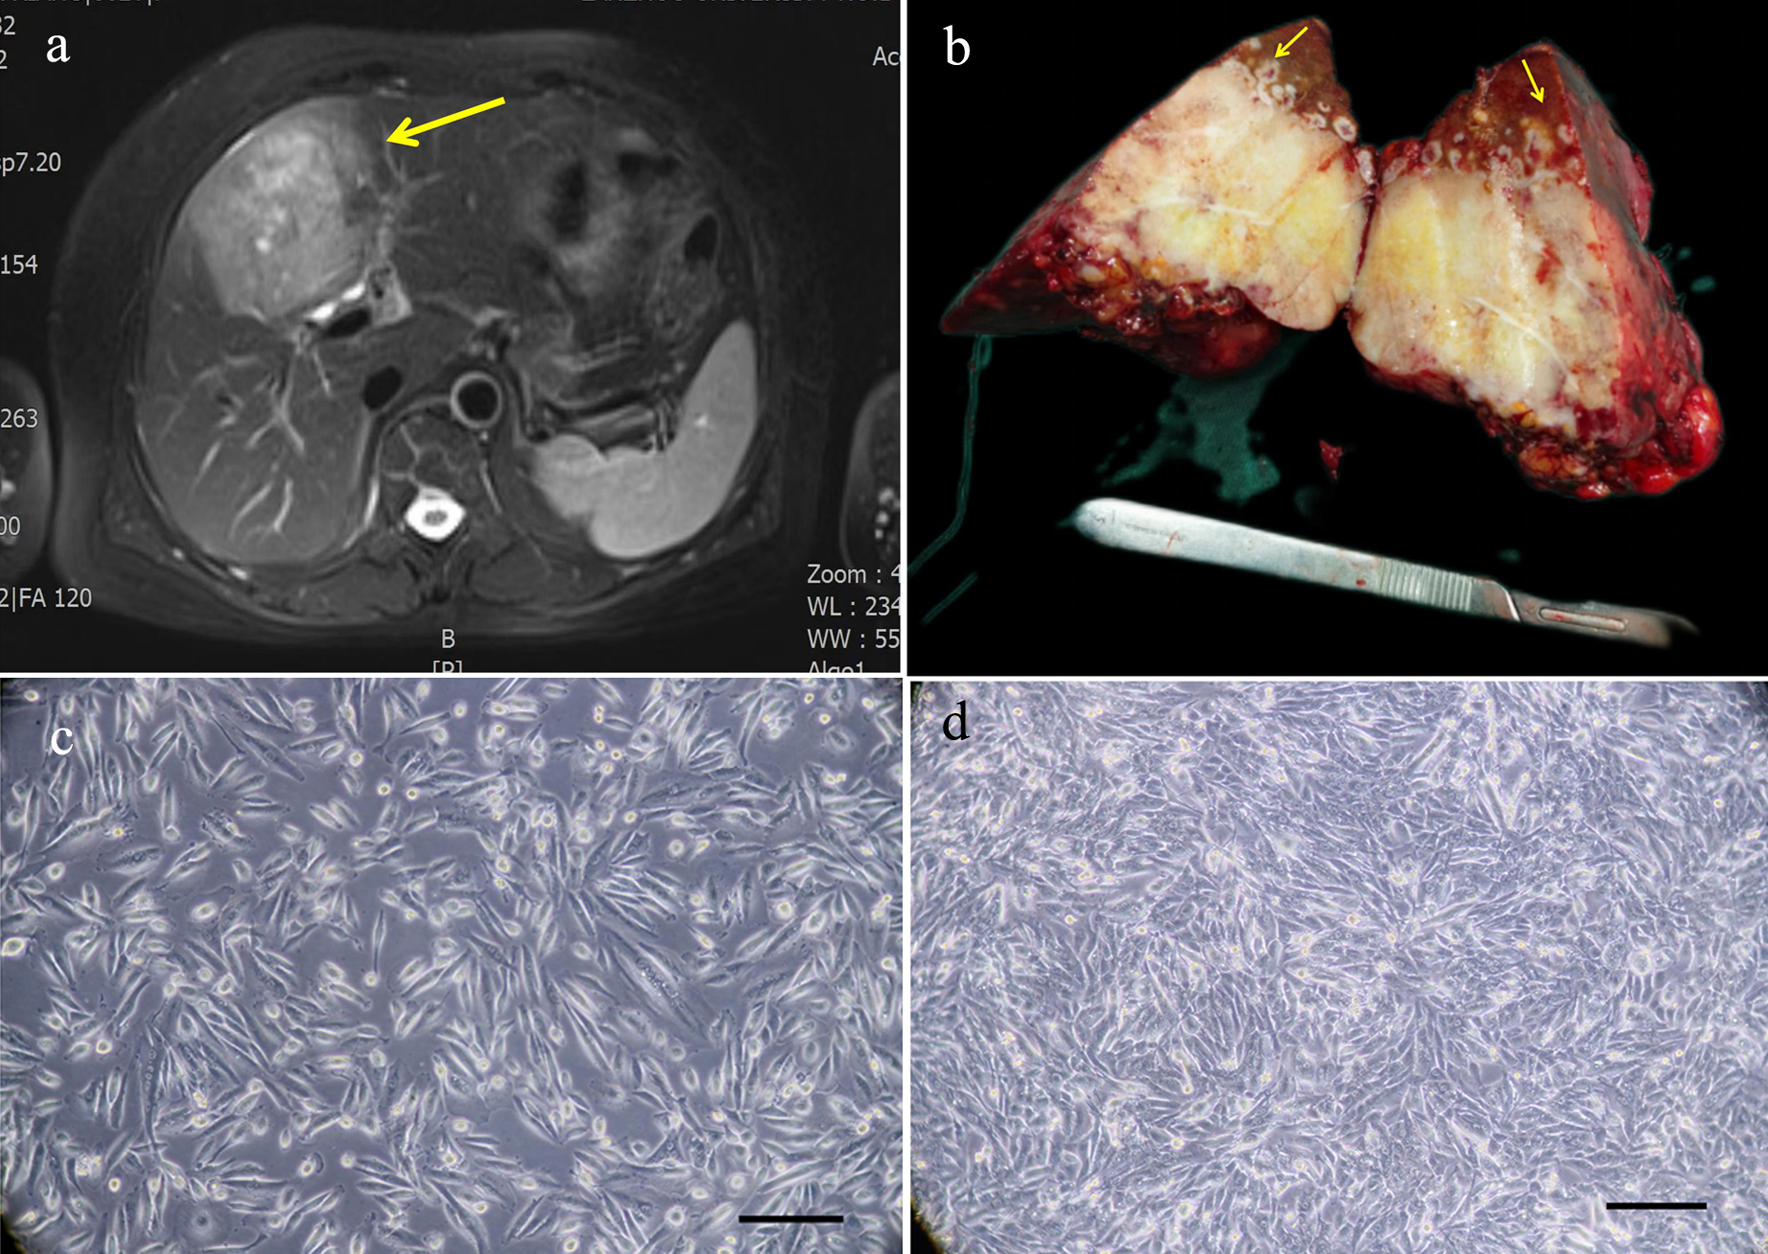

The tissue sample was collected from the tumor tissue of a patient with ICC who had undergone surgical treatment in the First Hospital of Lanzhou University on July 23, 2021. This patient was a 62-year-old female with a liver tumor and had no history of smoking, drinking, and hepatitis B and hepatitis C infections. The level of alpha-fetoprotein (AFP) in the patient was 7.8 IU/mL (reference range: 0 - 5.8 IU/mL), and the level of carcinoembryonic antigen (CEA) and carbohydrate antigen 19-9 (CA19-9) in the patient were within the normal range. The patient did not receive any preoperative treatment. The clinical data are shown in Table 1. Magnetic resonance imaging (MRI) showed that the tumor was in segment S4 of the liver, and had a size of 9 × 7 cm (Fig. 1a). The gross picture generally showed a huge tumor in segment S4 of the liver, with yellow and white sections and multiple satellite lesions around the tumor (Fig. 1b). The primary cells were extracted from the primary lesion and then subcultured.

![]() Click for large image | Figure 1. Relevant clinical data and morphology of the ICC-X2 cells. (a) MRI scan showing a large 9 × 7 cm lesion in segment IV of the liver (long arrow). (b) Gross view of the surgically resected specimen. Multiple satellite lesions can be observed around the primary lesion (short arrows). (c) Light microscope image of the ICC-X2 cells of passage 10. (d) Light microscope images of the ICC-X2 cells of passage 50 (scale bar = 100 µm). MRI: magnetic resonance imaging. |

Under the inverted microscope, it was observed that the cells were grown in a monolayer culture and lost contact inhibition. The cells were mainly spindle-shaped, and a few were polygonal and round (Fig. 1c). The cells had evident nucleoli. The cells maintained vigorous metabolism with each passage. The cell morphology and growth rate were stable, even after 80 generations (Fig. 1d).